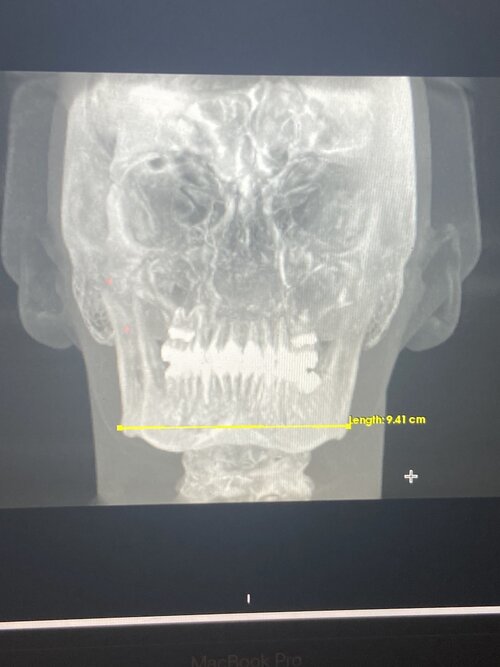

lets look at the bones:

lets look at the bones: